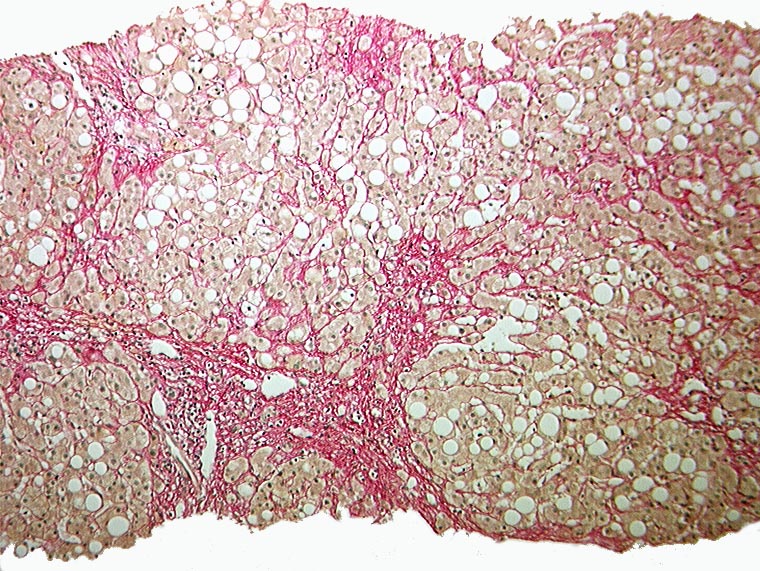

PathoPic ID 1095 - Sklerosierende Steatohepatitis, partieller zirrhotischer Umbau

Sklerosierende Steatohepatitis, partieller zirrhotischer Umbau

Grobtropfige Verfettung. Maschendrahtfibrose. Portoportale Septenbildung.

Unvollständiger zirrhotischer Umbau mit portoportaler Septenbildung.

Aethylabusus.

Histologie